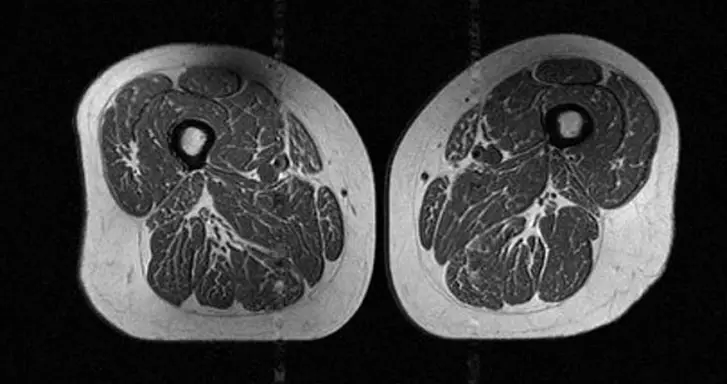

The first image shows a woman whose thigh muscles have minimal fat infiltration. She has a diet of 30 percent UPFs.

The second image shows a woman's thighs with greater marbling, and her diet consists of 87 percent UPFs.

Researchers found that greater consumption of UPF was linked to more apparent ‘marbling’, which describes when fat accumulates within the thigh muscles themselves and replaces healthy muscle tissue, leading to muscle weakening.

An MRI scan was done on each participant’s thighs, and researchers analyzed the scans and graded fat infiltration in the thigh muscles, including the hamstrings, quadriceps and inner thighs, on a scale from zero, which was no fat, to four, meaning greater than 50 percent fat.

When a participant increased their UPF consumption, muscle fat levels also rose. This startling finding was established in all muscle groups studied, including hamstring, quadriceps and inner thighs.

Researchers established that the people who ate and drank higher amounts of UPFs had far greater intramuscular fat, especially in the thighs.